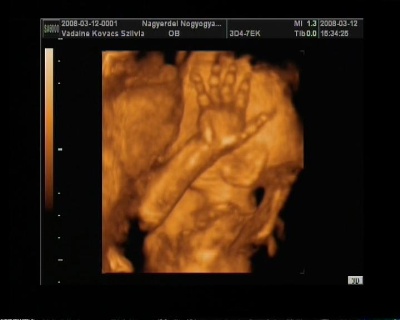

És egy tappancs 2008.03.08 19:45